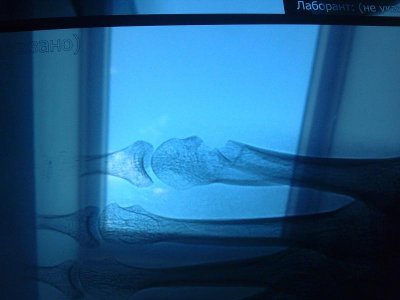

в клинике состояние ноги хирургу не понравилось. предложил сделать повторный рентген.

и он показал совершенно другую картину.

перелом V плюсней кости со смещением